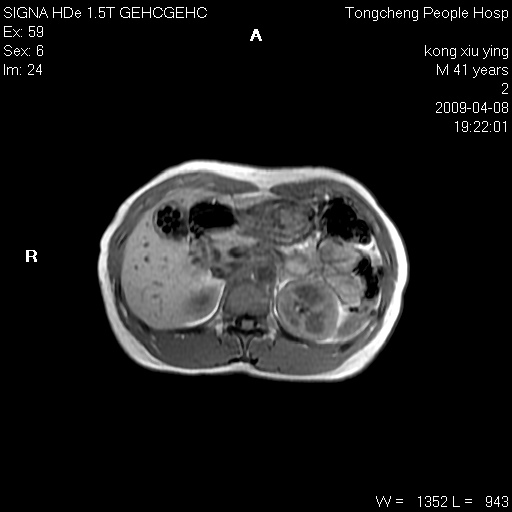

标题: CL1008:【经典】胆囊石榴籽样结石。

女,41岁。健康体检——彩超提示:胆囊显示不清。平素健康,无不适感。

腹部mr扫描及mrcp,图像如下: